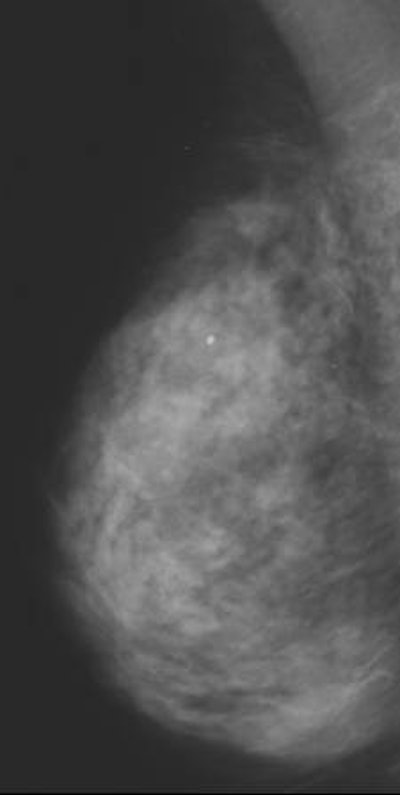

| In this study, one radiologist read baseline mammograms at the time of patient recruitment, and all follow-up mammograms at the end of the study. The second reader read all mammograms at the end, but was unaware of the imaging sequence. |

Mammograms from the National Health Service Breast Screening Programme were used as a baseline measure, with follow-up imaging done a year later. Warren and Sala assigned Wolfe patterns, and visually estimated the percentage density of each set of mammograms.

The results showed there was no difference in estimated percentage density at baseline, mean of 61.8% according to Warren and 61.6% based on Sala's read, or follow-up (58% and 57.4%, respectively). Mammographic density did decrease in both groups, but the difference between treatment and placebo was not statistically significant, the authors wrote.

According to Warren's read, 22% of the women in the isoflavone group changed to a more lucent Wolfe pattern versus 18% of the placebo group. There was no change for 78% and 80%, respectively, and only a 2% change to a denser Wolfe pattern in the placebo group.

According to Sala's read, 15% of those taking isoflavones exhibited a more lucent Wolfe pattern compared to 19% in the placebo group. Eighty-four percent of the women on isoflavones showed no change, as did 80% of the women taking the placebo. Finally, only 2% of both groups showed a denser Wolfe pattern.